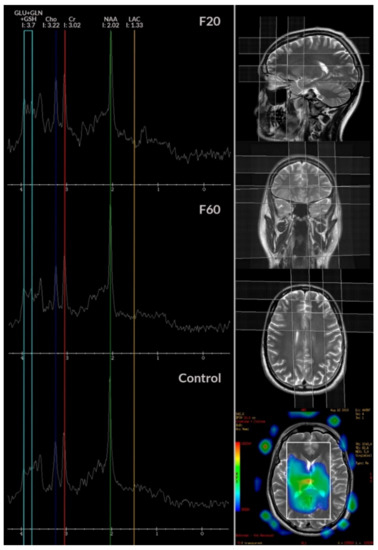

3.5. Neuroimaging Studies

| LIP 0.9–1.0 | 4,769,657 | 3,128,284.19 | 4,213,975.65 | 4923742.61 | 1,742,469.81 | 3,356,309.34 | 3,511,550 | 2,875,300 | 3,009,600 | γ2(2) = 2.25; p = 0.32 |

| LAC 1.33 | 3,986,255 | 3,590,129.03 | 5,347,930.43 | 1952562.47 | 2,290,871.91 | 3,373,001.8 | 3,807,050 | 2,926,600 | 4,250,700 | γ2(2) = 5.39; p = 0.07 |

| ALA 1.48 | 3,116,492.33 | 2,549,099.68 | 3,279,441.3 | 2250550.45 | 1,252,203.99 | 1,891,377.62 | 2,437,800 | 2,840,300 | 2,836,200 | γ2(2) = 1.06; p = 0.59 |

| NAA 2.02 | 35,592,666.67 | 21,412,329.03 | 26,459,343.48 | 49845895.22 | 8,148,541.71 | 7,783,049.3 | 25,970,000 | 23,198,000 | 25,634,000 | γ2(2) = 9.76; p = 0.008 |

| GLU 2.1 | 5,616,700 | 5,066,319.35 | 5,234,604.35 | 2145610.27 | 2,113,594.77 | 1,912,524.4 | 5,747,600 | 4,704,900 | 5,116,400 | γ2(2) = 1.04; p = 0.6 |

| GABA 2.3 | 11,950,866.67 | 7,924,832.26 | 7,804,804.35 | 23383742.18 | 4,695,692.97 | 4,519,643.27 | 7,798,100 | 6,683,600 | 6,726,100 | γ2(2) = 0; p = 1 |

| GLN 2.45 | 6,571,573.33 | 4,284,658.06 | 6,615,408.7 | 2911545.49 | 1,783,744.67 | 2,606,322.85 | 6,351,250 | 4,393,100 | 6,299,100 | γ2(2) = 18.33; p < 0.001 |

| CR 3.02 | 14,685,860 | 12,870,674.19 | 14,249,678.26 | 3213642.94 | 3,512,585.88 | 4,255,179.66 | 13,957,500 | 12,954,000 | 14,175,000 | γ2(2) = 4.56; p = 0.1 |

| CHO 3.22 | 11,826,310 | 10,704,625.81 | 12,965,773.91 | 4451263.58 | 2,963,926.23 | 5,022,070.96 | 11,776,000 | 10,469,000 | 1,283,1000 | γ2(2) = 3.99; p = 0.14 |

| GLC 3.43 | 4,469,010 | 3,242,659.03 | 5,493,995.65 | 2340956.02 | 1,348,296.84 | 3,839,775.13 | 3,975,650 | 3,187,100 | 4,424,400 | γ2(2) = 5.69; p = 0.06 |

| GLU + GLN + GSH 3.7 | 6,474,940 | 6,456,406.45 | 7,009,717.39 | 3,023,675.18 | 2,654,497.89 | 2,769,735.64 | 6,281,600 | 6,603,700 | 7,919,500 | γ2(2) = 0.58; p = 0.75 |

| GLC 3.8 | 7,791,786.67 | 5,946,009.68 | 6,798,052.17 | 3,690,099.48 | 2,795,699.54 | 3,126,442.87 | 7,434,450 | 5,737,500 | 5,663,300 | γ2(2) = 0.48; p = 0.09 |

| PCR + CR 3.9 | 12,587,493.33 | 10,337,651.61 | 16,627,239.13 | 5,680,273.03 | 5,179,535.32 | 26,591,342.08 | 12,107,000 | 9,643,300 | 12,864,000 | γ2(2) = 2.51; p = 0.29 |